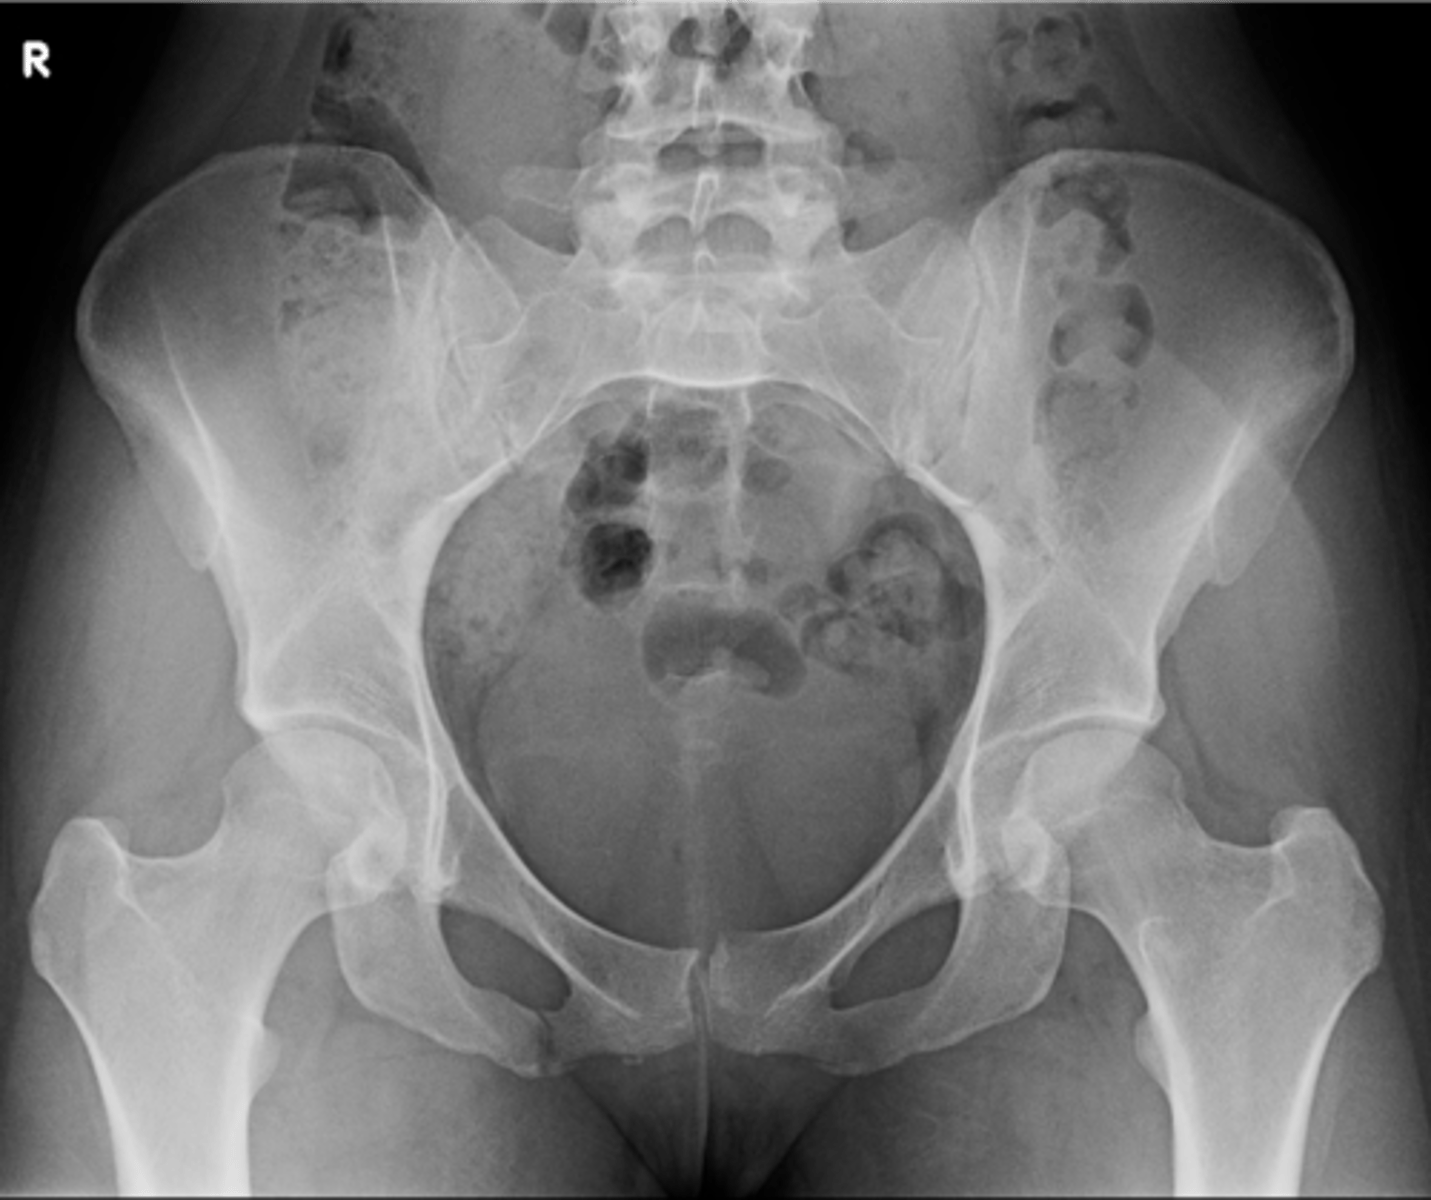

- AP pelvis

- Frog-leg pelvis

State the standard bilateral pelvis projections

AP pelvis

ID standard bilateral pelvis projection

Frog-leg pelvis